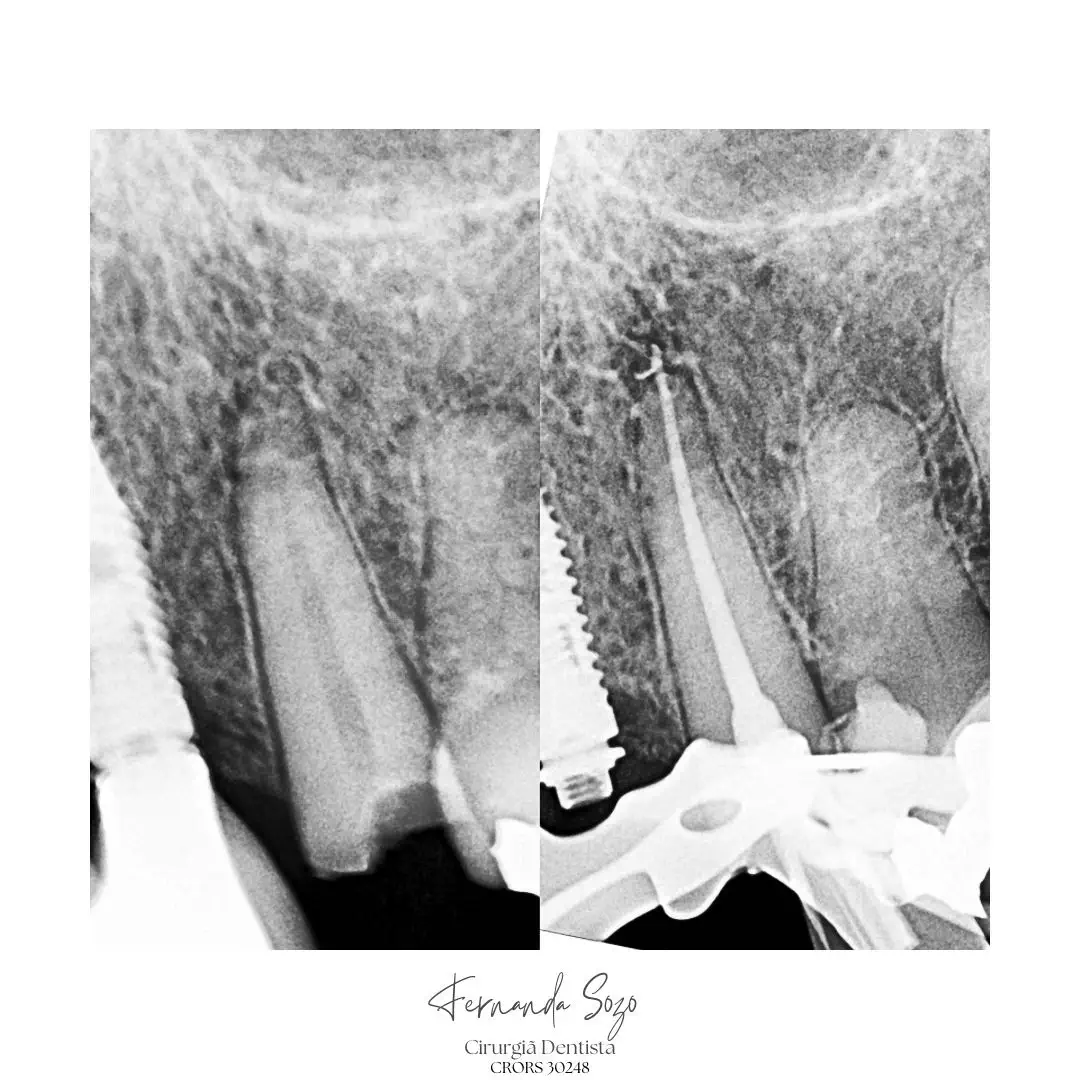

Portfólio

Casos Clínicos

Resultados que demonstram precisão técnica e excelência.